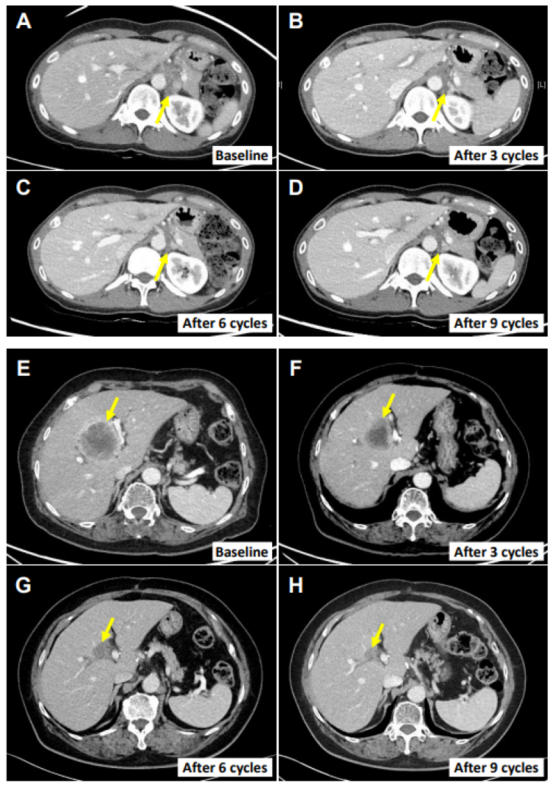

圖:其中2名患者的腫瘤消退影像情況

值得注意的是,患者E0107為一例40歲女性,因膽囊炎行膽囊切除術(shù),術(shù)后病理確診為膽囊癌合并腹膜癌。其病史中已包含使用吉西他濱、順鉑、5-氟尿嘧啶(5-FU)、伊立替康脂質(zhì)體及亞葉酸等多種化療藥物的治療經(jīng)歷。在采用NK細(xì)胞療法聯(lián)合帕博利珠單抗治療后,其轉(zhuǎn)移性淋巴結(jié)體積顯著縮小,減小幅度高達(dá)82.3%。